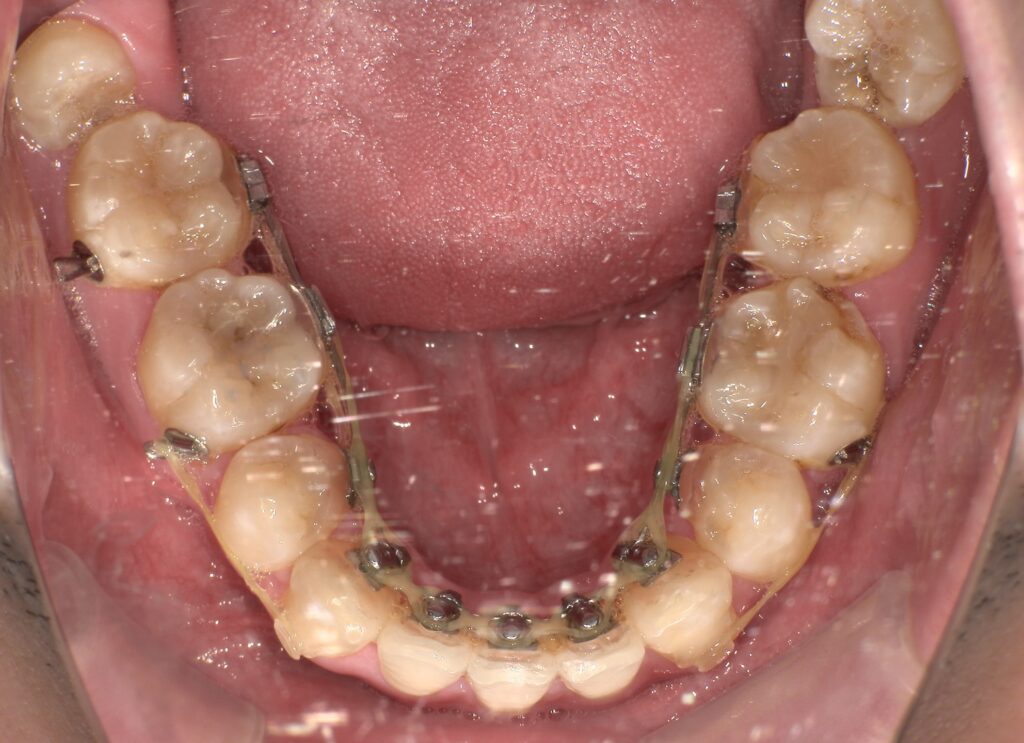

症例紹介

治療前

| 主訴 | 上の歯出てる、口元出てる |

| 診断名 | 上顎前突 |

| 年齢 | 20代男性 |

| 治療内容 | ブラケットを用いたインプラントアンカー2本埋入 |

| 抜歯非抜歯 | 抜歯あり 上44下55EXT |

| 期間 | 動的治療25ヶ月 |

| 費用 | 総額1,364,000(税込) |

| リスク、副作用 | 歯痛、虫歯、歯周病、口内炎、発音障害、歯根吸収、歯肉退縮、歯髄炎、顎関節症、歯の咬耗、エナメルクラック |